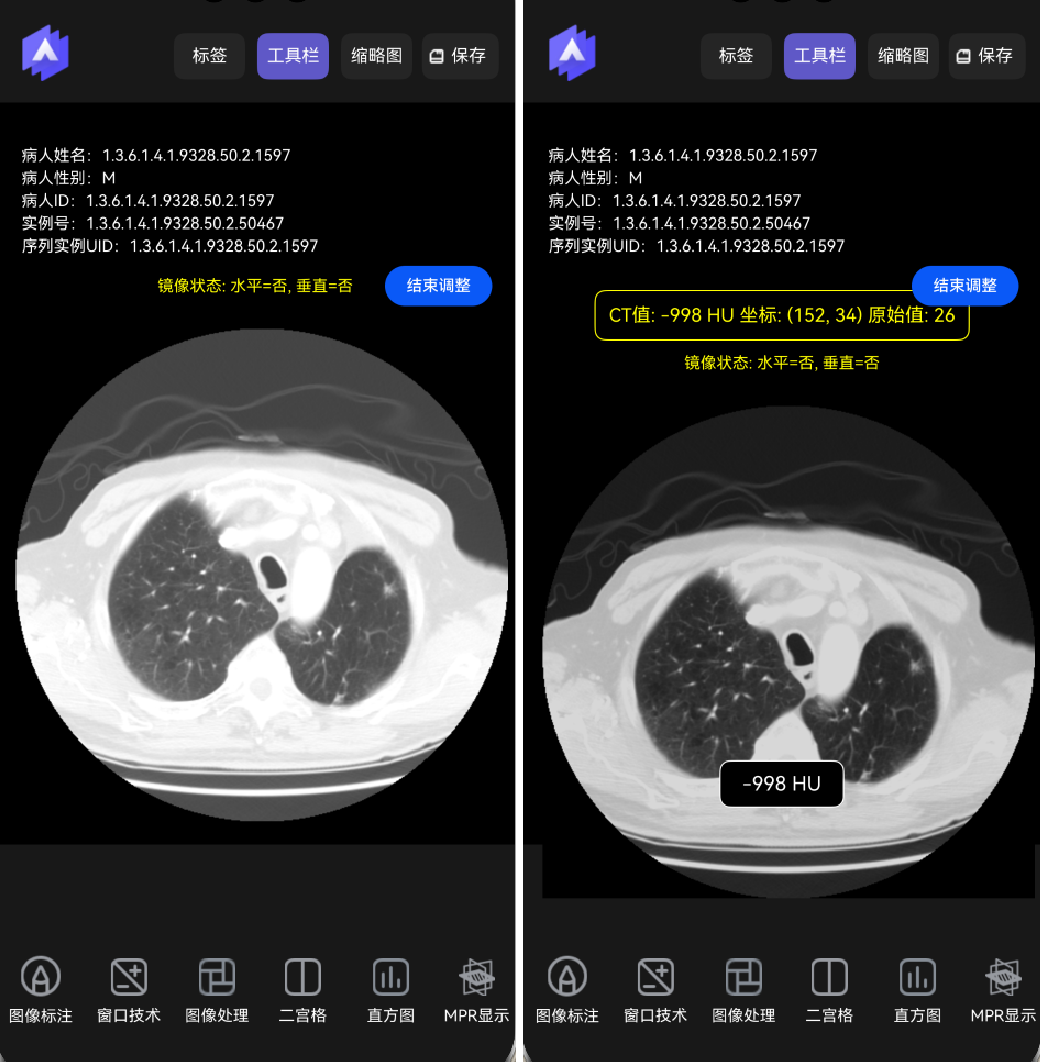

显示CT值。点击图像某个部位时在底部显示当前的CT值,如下图所示。